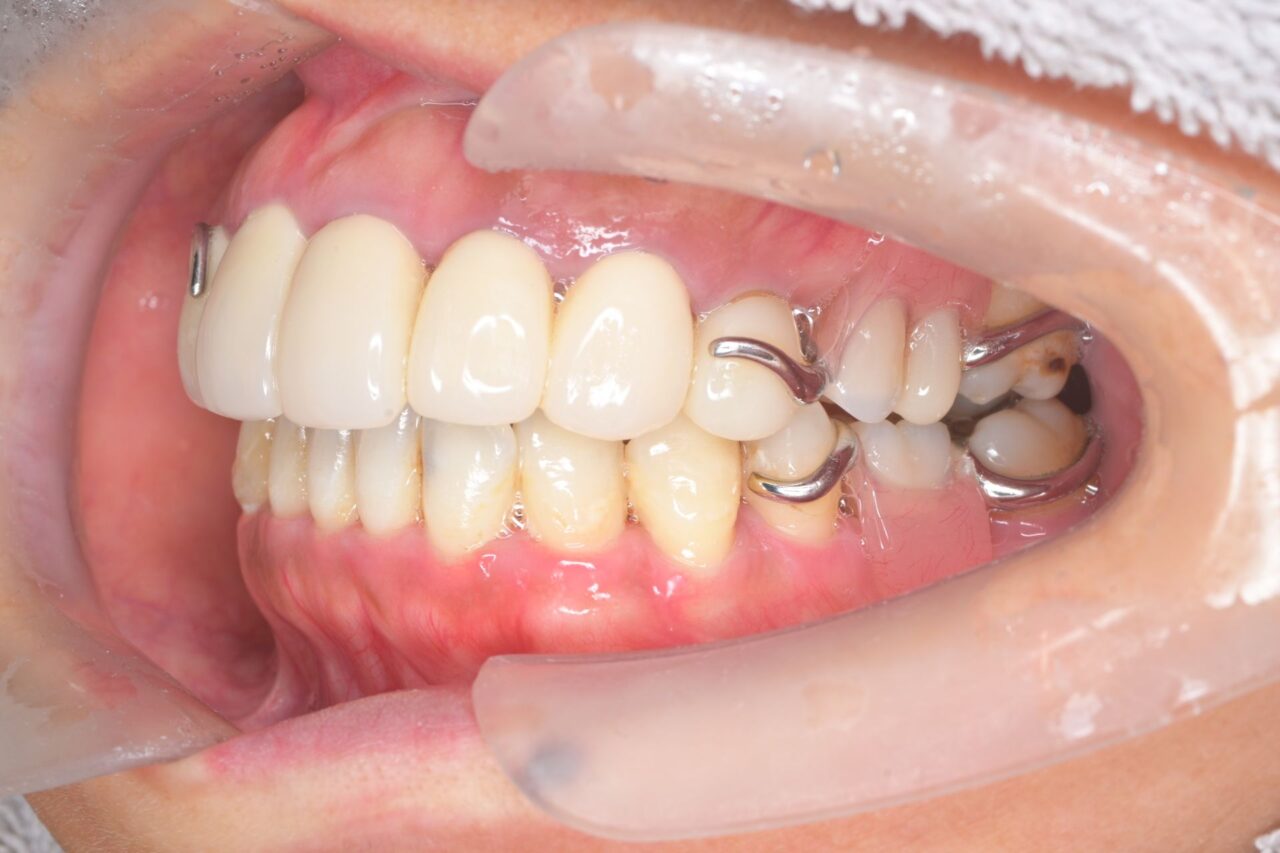

左側面

左右共に奥歯が無いので、歯の支えが全く無い状態です。これでは、お肉などを噛むことが出来ません。

さらに、舌も肥大化してしまっていますねぇ。

「前歯があるじゃん。」と思うかもしれませんが、前歯はうどんなどの柔らかいものを噛み切るための物で、決して硬いものを噛むための歯ではありません。柔らかい物ばかりを食べていると炭水化物が多くなってしまい糖尿病にもなりやすくなります。大切なのは奥歯です。